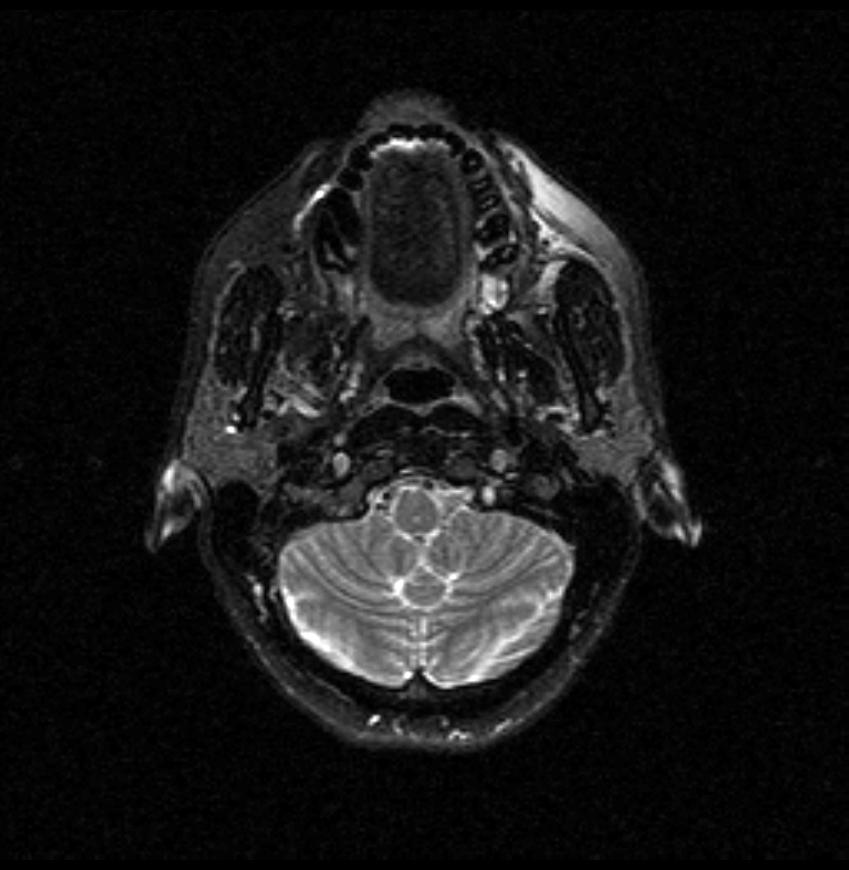

06.06.2011 МРТ - головы и шеи.

Пацентка 36 лет, с жалобами на припухлось в околоушной области справа.

В глубокой доле  правой околоушной железы  на фоне неизмененной паренхимы зона  гетерогенного по Т2, гипоинтенсивного по Т1  с единичными гиперинтенсивными включениями.При контрастировании- накопление контраста диффузное неоднородное и по периферии.Рискну предположить злокачественное образование ( аденокарцинома) с низкой степенью злокачественности( есть капсула, экспансивный рост).Сильно не расстреливайте.

Проблема в том, что перед челюстно-лицевым хирургом стоит распространенность любого объемного процесса, в данном случае все упирается в возмможную травму лицевого нерва и конечно же с дальнейшим его парезом, а ведь женщина  еще молодая. Образование имеет тонкостенную оболочку, по структуре неоднородно, с наличием кальцината, при этом МР-сигнал от окружающих анатомических структур(как костных так и мышечных) не изменен, т.е. об инфильтративном росте речи не идет, в какой то степени доброкачественное. В конкретном случае лицевой нерв с ретромандибулярной веной просто несколько оттеснен.

По гистологии аденома околоушной слюнной железы, но после удаления пока сохраняется парез лицевой мускулатуры, возможно временный.